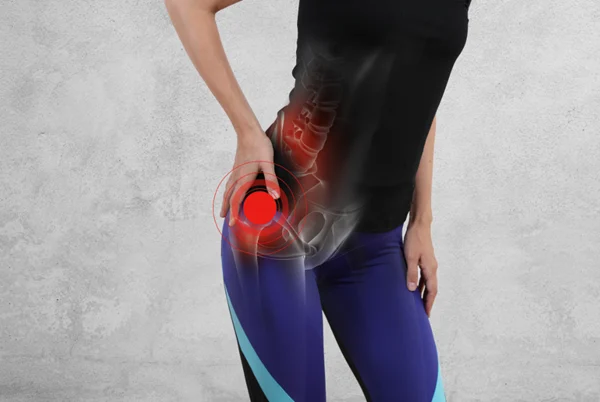

بورسیت لگن، شرایط رایجی است که بخش بیرونی کنار لگن و ران را در بالا تحت تاثیر قرار میدهد اما میتواند همچنین در ناحیه کشاله ران نیز احساس شود. بورسیت لگن، با التهاب بورس که یک کیسه ژله مانند قرار گرفته در لگن و همچنین در کل بدن است، ایجاد میشود.

این آسیب در بین دوندهها رایج است چون بر اثر استفاده بیش از حد و فشار تکراری ایجاد میشود. بورسها ماند ضربهگیر عمل میکنند تا اصطکاک بین استخوان و بافت نرم را کاهش دهند اما وقتی تحریک شده و ملتهب میشوند، باعث درد در آن نواحی خواهند شد.

دو نوع بورس بزرگ در لگن وجود دارد که بیشتر مستعد بورسیت هستند. دوندهها معمولاً در بخش بیرونی استخوان لگن (تروکانتر بزرگ) درد را احساس میکنند و التهاب این بورس، بورسیت تروکانتریک نامیده میشود.

بورسیت کمتر رایج، التهاب بورس تهیگاهی مازویی قرار گرفته داخل لگن (بخش کناری کشاله ران) است. اگرچه این شرایطی در مقایسه با بورسیت تروکانتریک، کمتر رایج است، اما به همان شیوه درمان میشود.

علائم به نوع بورسی که ملتهب شده است بستگی دارد، اما رایجترین علائم تجربه شده، درد کنار لگن بوده که اغلب در بالای ران احساس میشود و میتواند در باسن هم احساس شود. درد در حین دویدن احساس میشود اما همچنین میتواند در حین فعالیت روزانه نیز عود کند و ممکن است به لمس حساس باشد. ممکن است این مصدومیت با یک درد تیز قبل از اینکه به یک درد مبهم که در ناحیه بزرگتری از لگن پخش شده است، شروع شود.

فیزیوتراپیست هلن اولری در این باره میگوید: ” وقتی که روی بخش تحت تاثیر قرار گرفته در لگن دراز میکشید، میتوانید درد را احساس کنید”. و این درد میتواند بعد از نشستن، زمانی که میایستید، بدتر شود چون ناگهان، باید انقباضات زیادی در ناحیه لگنی برای بلندکردن شما به کار گرفته شود. همچنین در حین حرکت به اطراف، بالارفتن از پلهها، نیز درد بدتر میشود، چون این فعالیتها باعث درگیری بیشتر این نواحی میشوند.

رایجترین علامت، درد در بخش بیرونی لگن و بالای ران است. این درد ممکن است به صورت یک درد تیز شروع شده و سپس به دردی مبهم در ناحیه وسیعتری تبدیل شود. حساسیت به لمس، درد هنگام دراز کشیدن روی پهلوی درگیر، و درد هنگام بالا رفتن از پله یا بلند شدن از صندلی از دیگر علائم آن است.